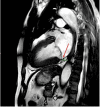

Figure 8

Figure 8. Cardiac MRI with an arrow indicating mild mitral annular disjunction (6.6 mm)

MRI: magnetic resonance imaging